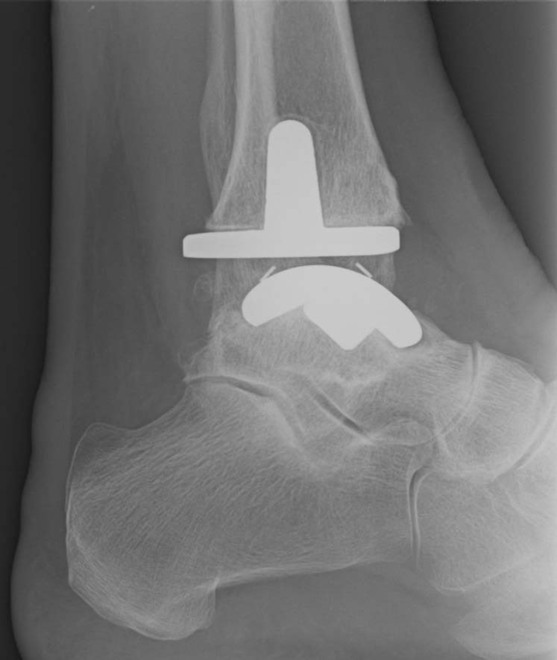

Prótesis de tobillo

Prótesis de tobillo La prótesis de tobillo es una técnica quirúrgica de muy buenos resultados ...